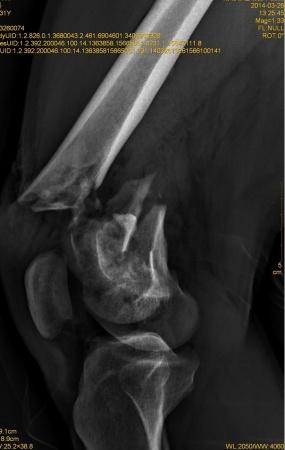

右股骨远端开放性粉碎性骨折

患者XXX,男,31岁,农民。高空跌伤致右大腿畸形伴活动性出血1小时入院。患者一般情况可,体重80kg。完善相关辅检,入院诊断:1.右股骨远端开放性粉碎性骨折;2.右髌骨粉碎性骨折;3.右桡骨远端骨折。入院后行右股骨开放性骨折清创缝合术+右胫骨结节骨牵引术,布朗支架抬高制动,目前患者右大腿远端肿胀明显,给予抗感染,消肿止痛等对症支持治疗。 2014-3-19,爱爱医***里mimi98发了类似的帖子,我刚好也遇到了同样的病例,诚心向各位老师、战友寻求好的治疗方案。